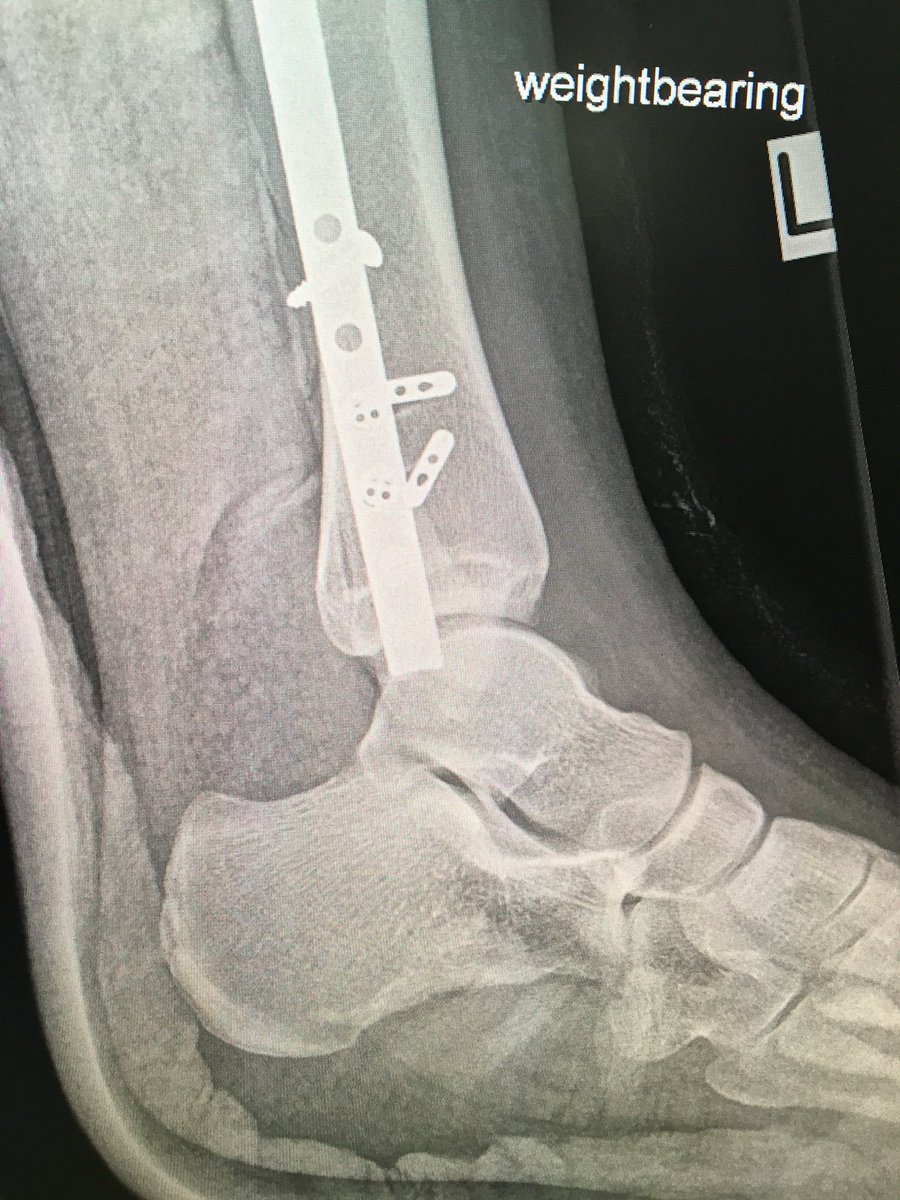

When the syndesmosis is over compressed, the talus is spit forwards. It’s subtle if you’re not looking for it, but once you see it, don’t neglect it. It’s a subluxed incongruent ankle joint. #OrthoX

See what’s wrong here?  The large clamp across the ankle is not ‘reducing’ the syndesmosis, it is ‘over compressing’ it. There is a reason we use Position screws across the syndesmosis and not Lag screws. Don’t over compress the syndesmosis, it will push/spit the Talus. #OrthoX